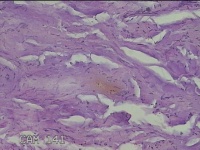

肛周外痔

1.出血性内痔 2.混合痔 3.肛乳头肥大

一般病史

间断便血3年余。

标本名称

大体所见

灰白暗红色包块0.7x0.3x0.2cm一个,表面糜烂。

像痔。

有可能是外痔。猜的。